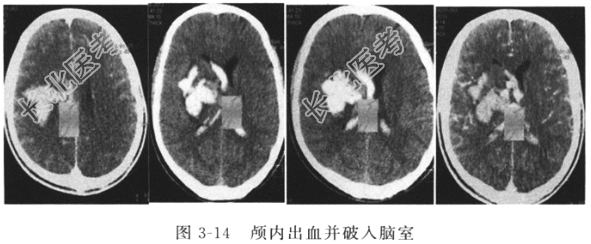

病情患者,男,39岁,因头痛1个月,突发意识障碍4天,伴呕吐、左侧肢体乏力,于2013年2月1日抬送入院。既往有高血压史,吸烟史十余年,否认传染病病史,无食物及药物过敏史。护理体查:T38.0℃,P99次/分,R22次/分,BP132/80mmHg,意识浅昏迷,GCS评分E2V3M5=10分,双侧瞳孔等大等圆2mm,对光反射迟钝,皮肤、黏膜色泽正常,无水肿、无皮疹、无出血,全身浅表淋巴结未触及肿大,耳、鼻无分泌物,双肺呼吸音粗,无干湿啰音,心律齐,心音正常,无杂音,腹部外形正常,无压痛、无反跳痛、无包块,肠鸣音正常,无移动性浊音,无肾区叩击痛,肝、脾、胆囊未扪及,外生殖器、脊柱正常,四肢肌张力正常、右侧肌力Ⅲ级,各浅反射及膝腱反射正常,病理反射阴性。辅助检查头部CTA示颅内动静脉畸形,CT示颅内出血并破入脑室(图3-14)。